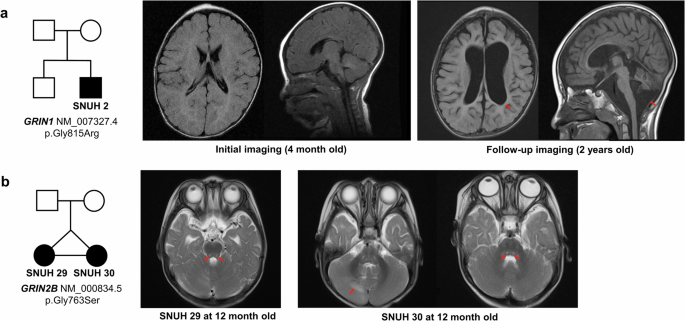

Representative cases of GRIN-related NDDs are presented in Fig. 1. Figure 1a shows a patient who visited our clinic with a chief complaint of GDD, along with seizures and microcephaly. Initial brain MRI revealed delayed myelination, whereas follow-up imaging revealed diffuse brain atrophy. Trio whole-exome sequencing (WES) identified that the patient had a de novo missense mutation in the GRIN1 gene (c.2443G>C) located within the M4 helix of the TMD. The patient expired with an unknown etiology at the age of 2 years and 11 months of age. Figure 1b shows monozygotic twins with the chief complaint of GDD. Notably, both patients presented very similar MRI findings, including nodular T2 hyperintensities in the brainstem (SNUH 29 and SNUH 30) and cerebellum (SNUH 30). They both presented with profound GDD with an inability to speak meaningful words and walk independently.

a Clinical information of SNUH 2, who presented with a chief complaint of profound GDD at four months of age. The patient was found to have a de novo GRIN1 missense variant located in the M4 helix of TMD (c.2443G>C, p.Gly815Arg). An initial brain MRI acquired at four months of age showed delayed myelination, while follow-up imaging at two years old showed diffuse brain atrophy. b Clinical information of SNUH 29 and SNUH 30, monozygotic twins presenting with a chief complaint of profound GDD. Quartet whole-exome sequencing analysis identified a de novo GRIN2B missense variant (c.2287G>A, p.Gly763Ser) in both twins. Brain MRI acquired at 12 months old revealed nodular T2 hyperintensities in the brainstem (SNUH 29, SNUH 30) and cerebellum (SNUH 30). TMD transmembrane domain, GDD global developmental delay, MRI magnetic resonance imaging.

As demonstrated in representative cases, patients with GRIN-related NDDs typically present with profound GDD during infancy, which is characterized by limited developmental progress. Previous studies have reported that the MRI findings of patients with GRIN-related NDDs include cortical atrophy and increased white matter signal intensity in the periventricular white matter17,18. To our knowledge, the MRI findings shown in Fig. 1b have not been previously reported. We hypothesize that these features may be attributed to a genetic etiology and could be distinctive characteristics of GRIN variants. Notably, identical findings were observed in the monozygotic twins, further supporting the genetic basis of these manifestations.